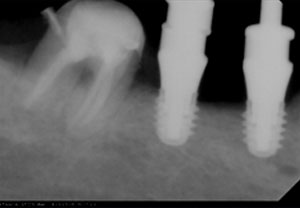

Στις ελάχιστες περιπτώσεις που ένα δόντι δεν μπορεί να σωθεί, δεν θα διστάσουμε να το αντικαταστήσουμε με ένα εμφύτευμα. Η εμφυτευματολογία αποτελεί μια έγκυρη θεραπευτική επιλογή αντικατάστασης δοντιών που δεν σώζονται, με όσο το δυνατό πιο αισθητικό και συντηρητικό τρόπο. Η χειρουργική τοποθέτηση των εμφυτευμάτων πραγματοποιείται από τον εμφυτευματολόγο κ. Μπαρμπετσέα Ανδρέα, ενώ στη συνέχεια η προσθετική αποκατάσταση επί των εμφυτευμάτων , πραγματοποιείται στο ιατρείο μας.